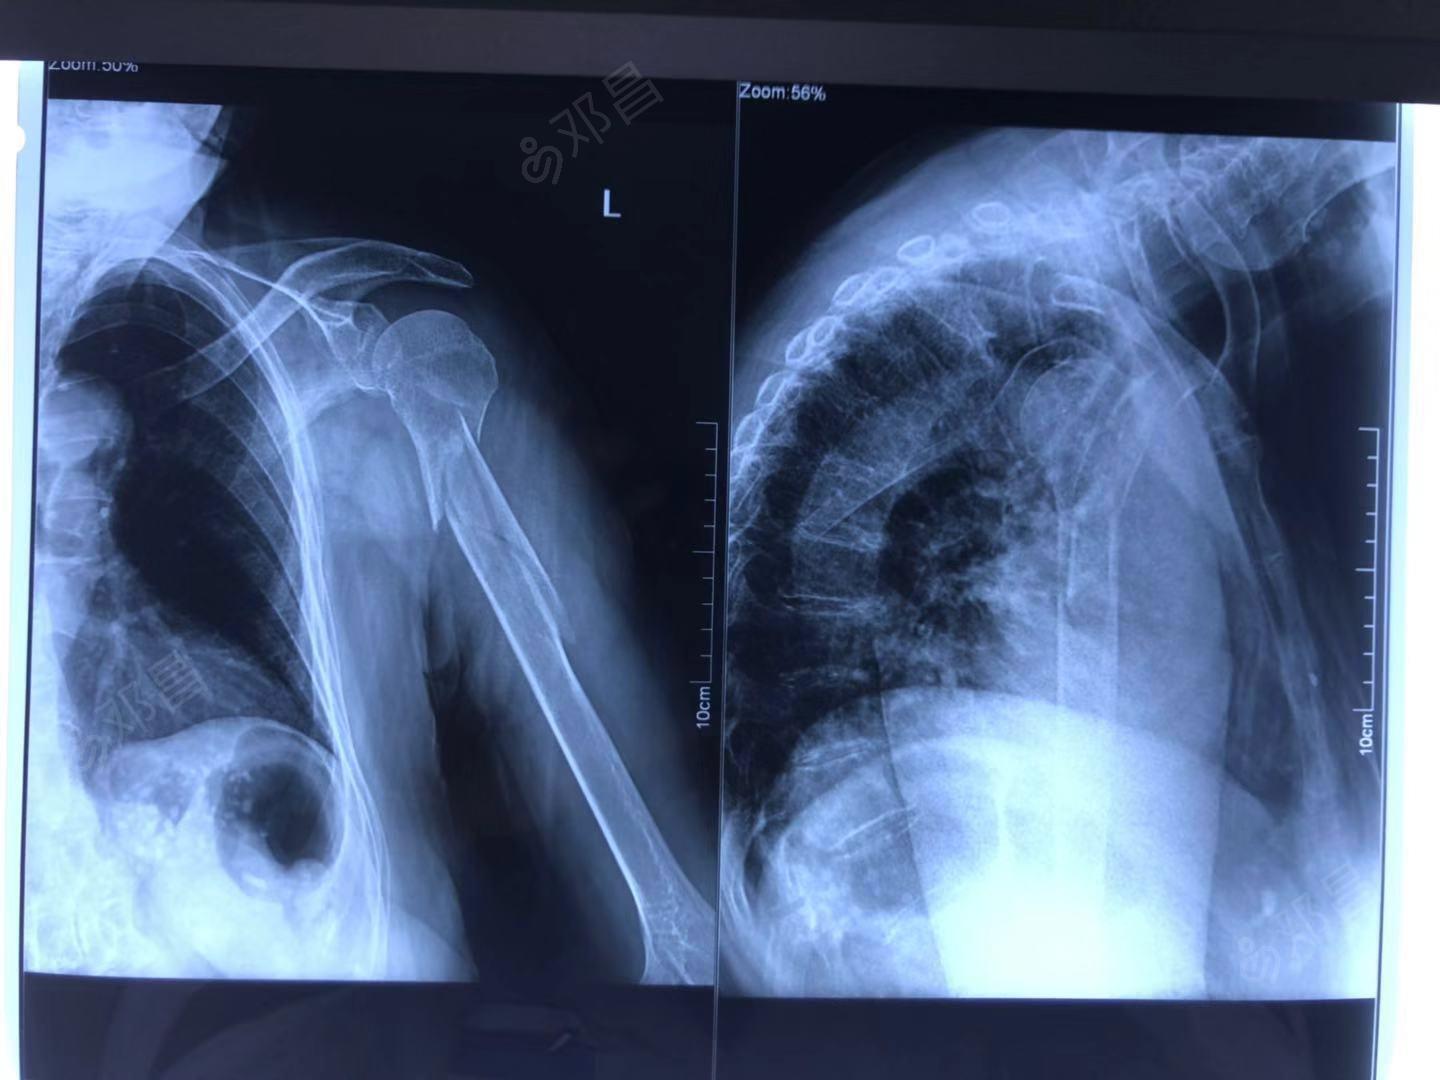

肩肱骨骨折,有x光片,请医生咨询

肱骨大结节骨折?脱位?请会诊如图